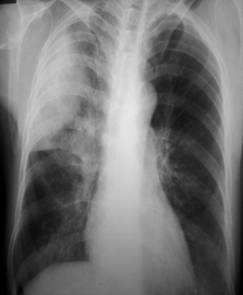

照片名称:右侧胸腔积液